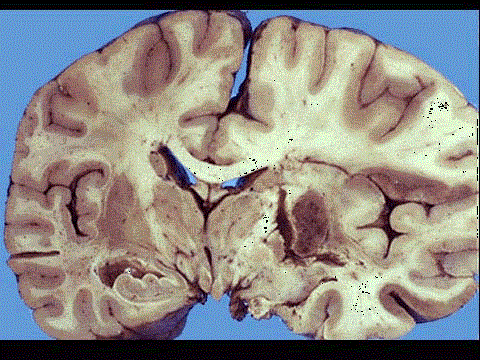

问题 图为脑梗死的肉眼及镜下观,叙述不正确的是 ( )

选项 A.多为贫血性梗死 B.若梗死区血供部分恢复,血液再灌注则可转变为出血性梗死 C.矢状窦血栓形成造成的梗死为出血性梗死 D.脑梗死时组织坏死多属于液化性坏死 E.大脑中动脉栓塞导致的脑梗死其栓子多来自于门静脉系统

答案 E